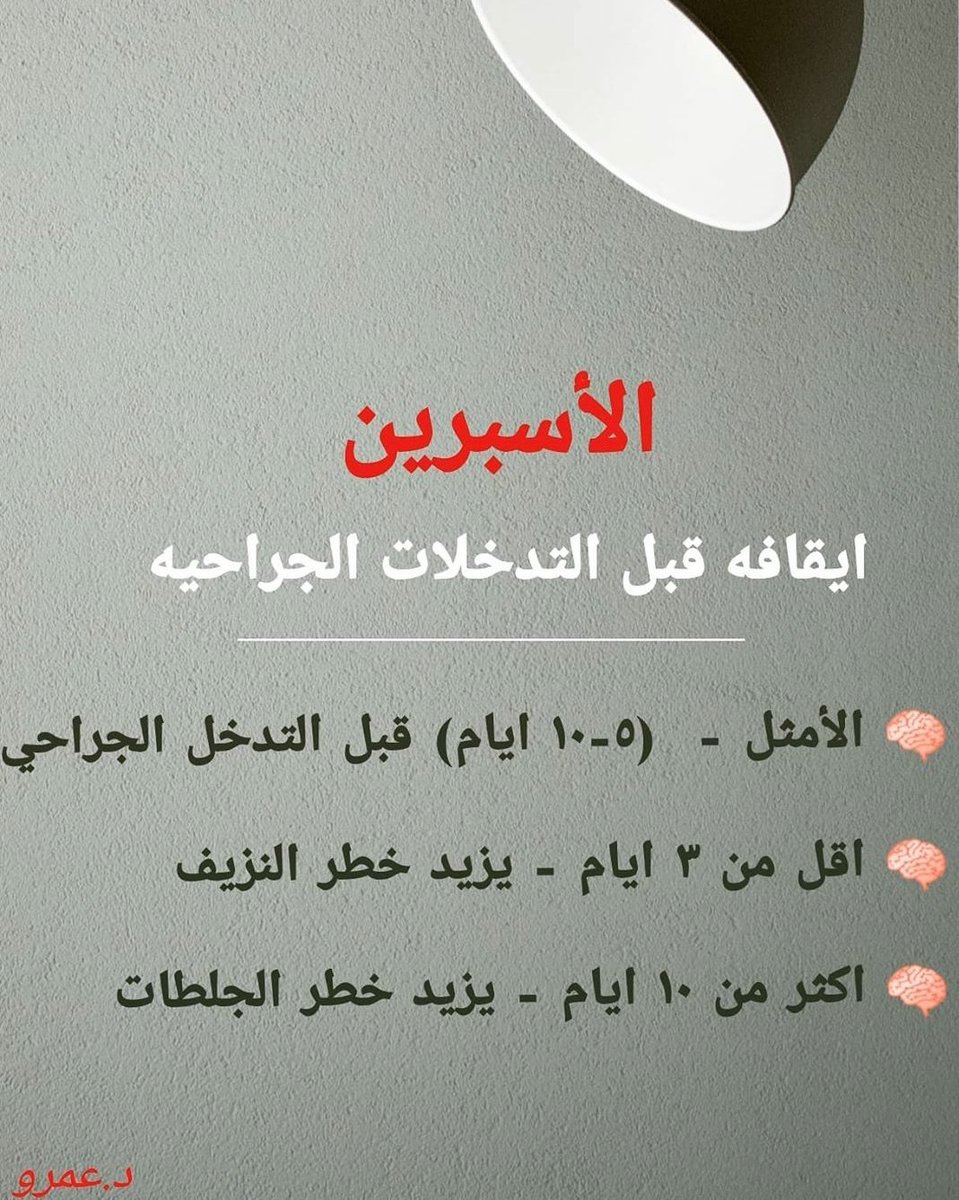

#السكته_الدماغيه_الاقفاريه

🧠العلاج الوقائي

خطوة هامه لمنع إعادة الاصابه مستقبلا

(معرفة السبب الأساسي والسيطرة عليه)

♦️متابعة

(سكر/ضغط/كوليسترول/تدخين/رياضه)

♦️الأسبرين أو ماشابه مدى الحياه

♦️علاجات سيوله اقوى للضرورة كارتجاف القلب الاذيني

♦️عمل دعامات حال وجود تضيق في الشرايين